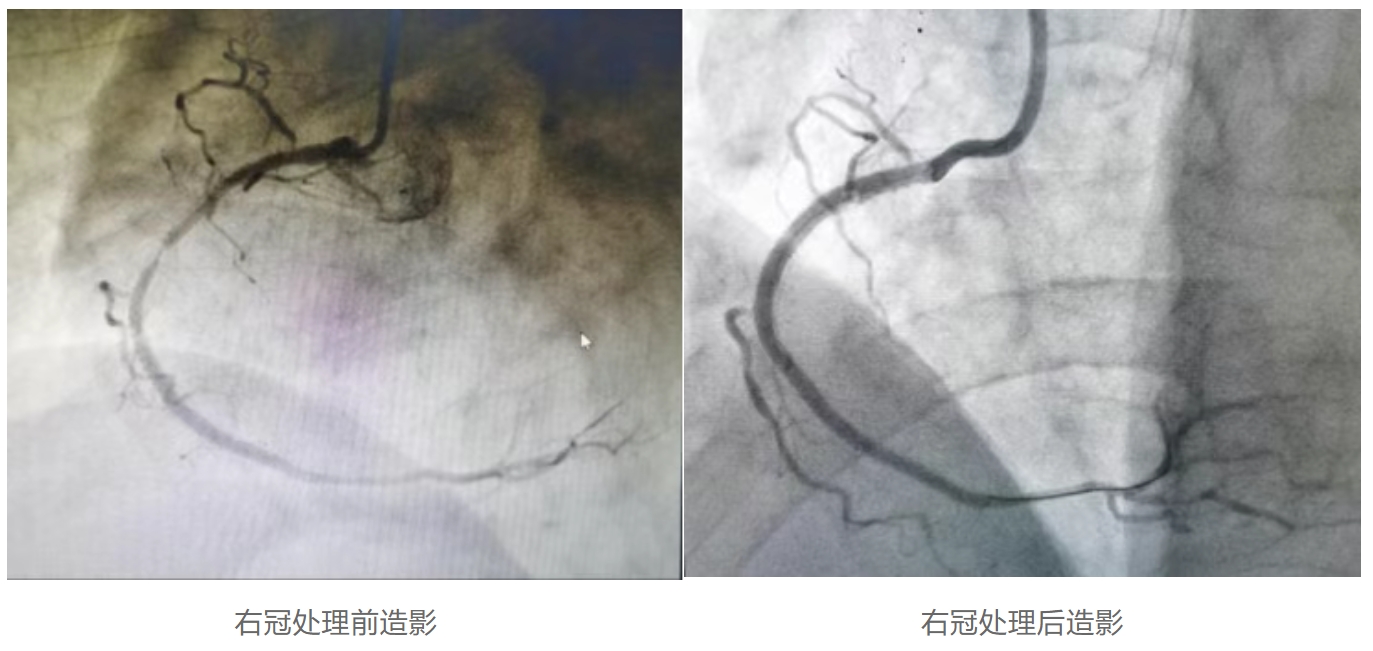

右冠处理情况:右冠处理前IVUS提示斑块负荷75%,管腔面积1.93mm²,经准分子激光斑块消蚀术处理后斑块负荷19%,管腔面积6.55mm²。